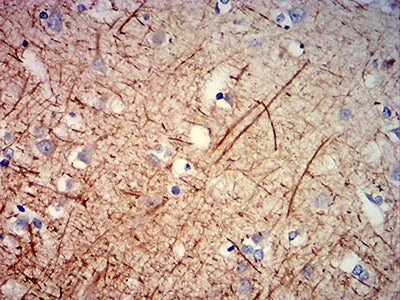

分类: 科研抗体货号: 31908别名: NFH; CMT2CC应用: IHC反应种属: Human

-